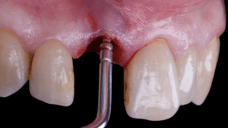

The surgical protocol began with the atraumatic extraction of tooth 1.1 to preserve as much of the alveolar socket as possible. Immediately following extraction, an N1 implant was placed into the socket using a guided surgical approach to ensure ideal three-dimensional positioning. The “one abutment one time” technique was applied to minimize soft tissue manipulation during the healing phase, which is particularly important in esthetic areas.

On the same day as the surgery, an immediate-load provisional crown was delivered. This restoration was fabricated in acrylic resin and screw-retained on the implant, following the “one abutment one time” principle. The provisional crown was carefully adjusted to avoid occlusal loading while supporting the peri-implant soft tissue architecture during the healing phase.